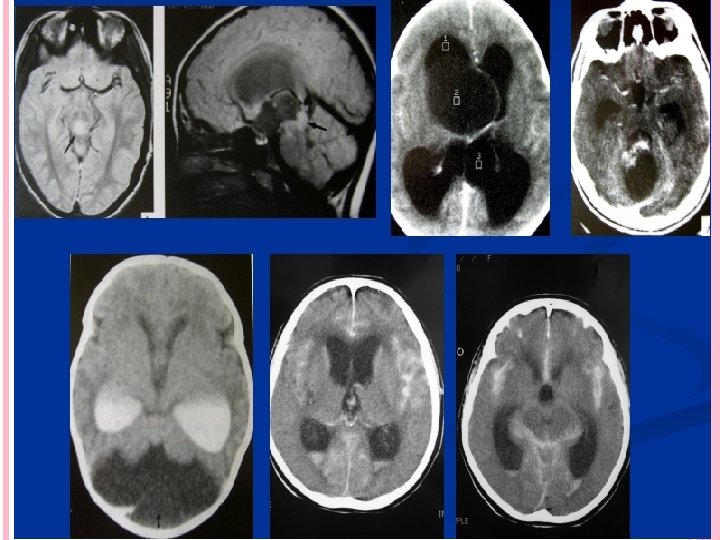

MALFORMACIÓN DE CHIARI Es una malformación que se asocia a mielomeningocele y estenosis de acueducto, caracterizado con descenso de alguna de las estructuras que ocupan fosa posterior por debajo del agujero magno Chiari 1891 MALFORMACIÓN DE CHIARI Hidrocefalia congénita SIRINGOMIELIA HIDROCEFALIA 10% Elongación y desplazamiento caudal de las amígdalas cerebelosas y porciones inferiores de los hemisferios cerebelosos por debajo del plano del agujero magno. Desplazamiento caudal de vermis cerebeloso, bulbo, protuberancia y IV ventrículo MIELOMENINGOCELE 80% HIDROCEFALIA

SÍNDROME DE DANDY WALKER Es una variedad de hidrocefalia congénita asociada a malformación de vermis cerebeloso y techo del cuarto ventrículo Imperforación de agujeros de Lushcka y Magendie LA MAYOR AFECCIÓN ES SOBRE EL 4 to. VENTRÍCULO, DILATADO FORMANDO BOLSA QUÍSTICA EN FOSA POSTERIOR HEMISFERIOS CEREBELOSOS APLANADOS Y RECHAZADOS HACIA LOS PEÑASCOS AGENESIA O DISFUNCIÓN DE CISTERNAS COMPROMISO EN LA CIRCULACIÓN Y REABSORCIÓN Villarejo Francisco. Martínez Lage Juan F. “NEUROCIRUGÍA PEDIÁTRICA”. Ediciones Ergón. Madrid España 2001

ANGIOGRAFÍA CEREBRAL Antes era fundamental el estudio del síndrome hidrocefálico, actualmente han quedado relegadas. Solo se utilizan para estudio de malformaciones vasculares que pudieran desencadenar hidrocefalia TOMOGRAFÍA CEREBRAL MÉTODO DE ELECCIÓN Tamaño de Cavidades ventriculares Causa Etiológica Villarejo Francisco. Martínez Lage Juan F. “NEUROCIRUGÍA PEDIÁTRICA”. Ediciones Ergón. Madrid España 2001 Neumoencefalografía Ventriculografía Cisternografía isotópica

Criterios para TAC Presencia de dilatación ventricular Hipodensidad en polos occipitales y frontales periventriculares Borramiento de los surcos cerebrales INDICE DE EVANS : igual o superior a 0. 30 debe considerarse patológico Cuernos temporales con diámetro mayor a 2 mm Lopez Ojeda Pablo, DIAGNOSTICO Y TRATAMIENTO DE LA HIDROCEFALIA CRONICA EN EL ADULTO, Barcelona hospital universitario 2009

RESONANCIA MAGNÉTICA HALLAZGOS EN RM Desproporción entre dilatación ventricular y surcos corticales Hipodensidades periventriculares 3 ventrículo redondeado Astas frontales contornos abombados Adelgazamiento y estiramiento del cuerpo calloso